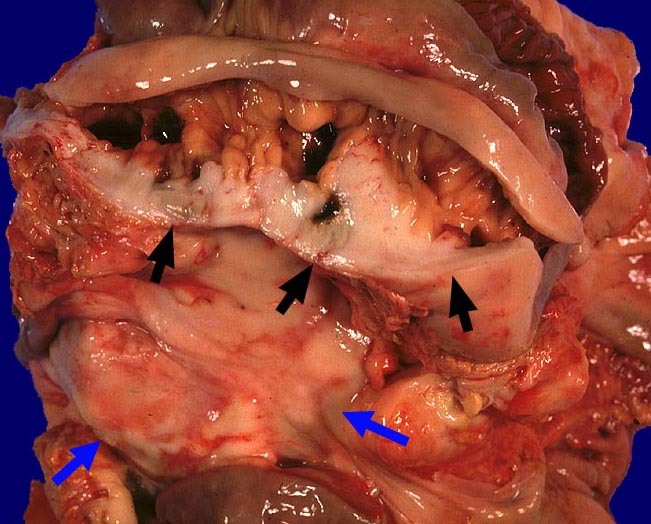

Diffuses grosszelliges B-Zell-Lymphom (WHO)

Mesenterium

Eröffnetes Jejunum mit anhaftendem Mesenterium. Das Mesenterium und die Jejunumwand sind diffus lymphominfiltriert.

Befall abdominaler Lymphknoten.